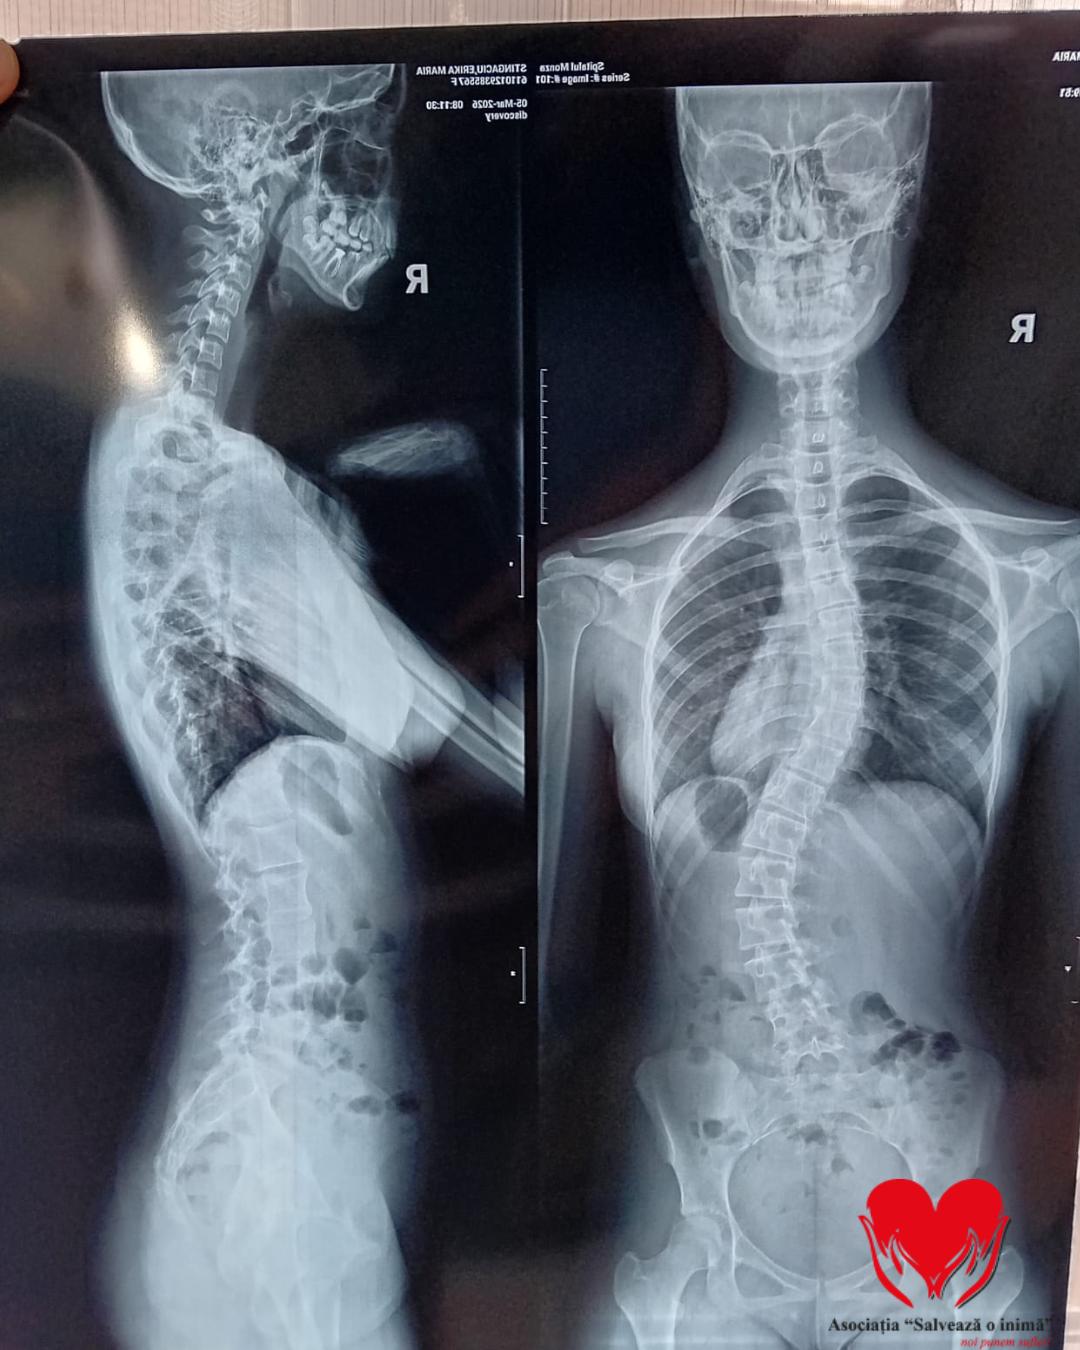

Erikai Maria Stingaciu este o adolescentă de 15 ani care se confruntă cu un diagnostic sever de scolioză dorsolombară progresivă, o afecțiune care îi modifică zilnic postura și îi afectează profund calitatea vieții.

Până în urmă cu doi ani, Erika era un

copil obișnuit, cu planuri simple și o copilărie trăită firesc. Totul s-a

schimbat în februarie 2024, când, în urma unui consult aparent banal, medicul a

observat o asimetrie la nivelul umerilor. Investigațiile ulterioare au condus

la stabilirea diagnosticului de scolioză idiopatică lombară, iar de atunci

viața ei a devenit o luptă continuă pentru a încetini evoluția afecțiunii.

A urmat zilnic ședințe de kinetoterapie, a

purtat un corset rigid tip Cheneau timp de 23 de ore din 24 și a trecut prin

multiple consultații și investigații în centre medicale din țară. În ciuda

tuturor eforturilor, evoluția a continuat, iar în februarie 2026, în urma unui

nou control, medicii au confirmat caracterul progresiv al scoliozei și

necesitatea unei intervenții chirurgicale.